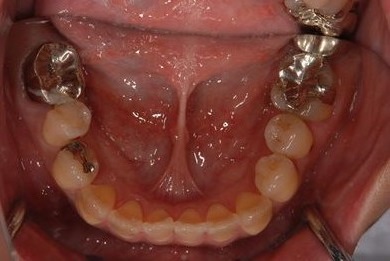

治療前

• 治療前